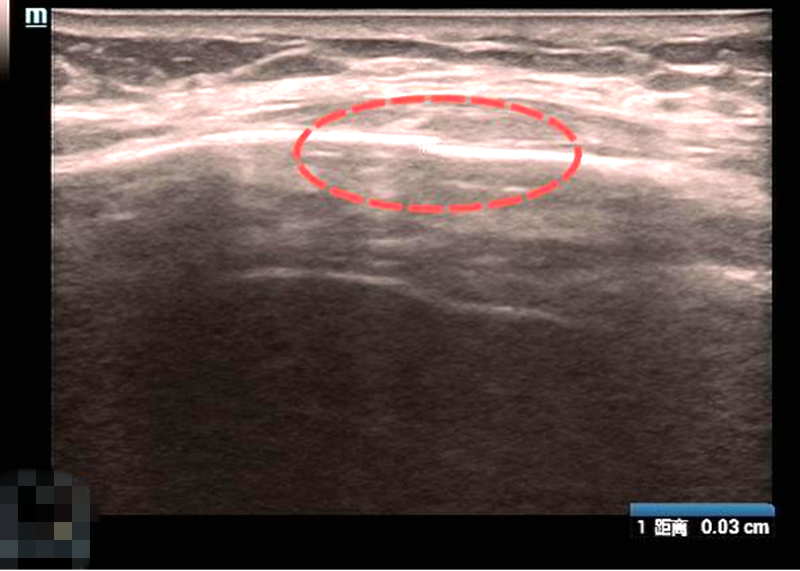

近日,一位56岁患者因胸痛来到超声医学科就诊,自述疼痛剧烈,甚至不敢用力呼吸,希望明确病因。超声检查乳腺未见明显异常,但医生在查体时发现其局部有明显按压痛,经追问病史得知,患者一周前在家抱孙子时曾被踢中胸部,当时仅感轻微隐痛,未予重视,随后疼痛逐渐加重,咳嗽或翻身时如针扎一般,自行贴敷止痛膏药也未见缓解。随后医生为其进行肌骨超声检查,最终确诊为左侧第5前肋骨线性骨折。这类因摔倒、撞击等外力导致的肋骨损伤在临床中十分常见,很多人因初期症状轻微而忽视,导致延误诊治。接下来我们将结合这个病例来具体了解肋骨骨折的典型表现、超声检查的优势以及科学的应对措施。

该患者就诊后,我们首选肌骨超声检查,其优势远超传统X线检查,具体如下:

2.精准高效:能清晰识别X线易漏诊的线性骨折,同时观察软组织水肿情况,实时动态判断骨折是否移位,当场出报告;

最终我们通过超声确诊患者为轻微线性骨折,无移位、无肺部损伤,为治疗提供精准依据。